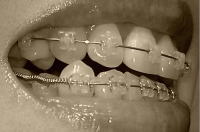

右側

beforeR.jpg 矯正前(^-^;)

060908b.jpg 9月8日

061006c.jpg